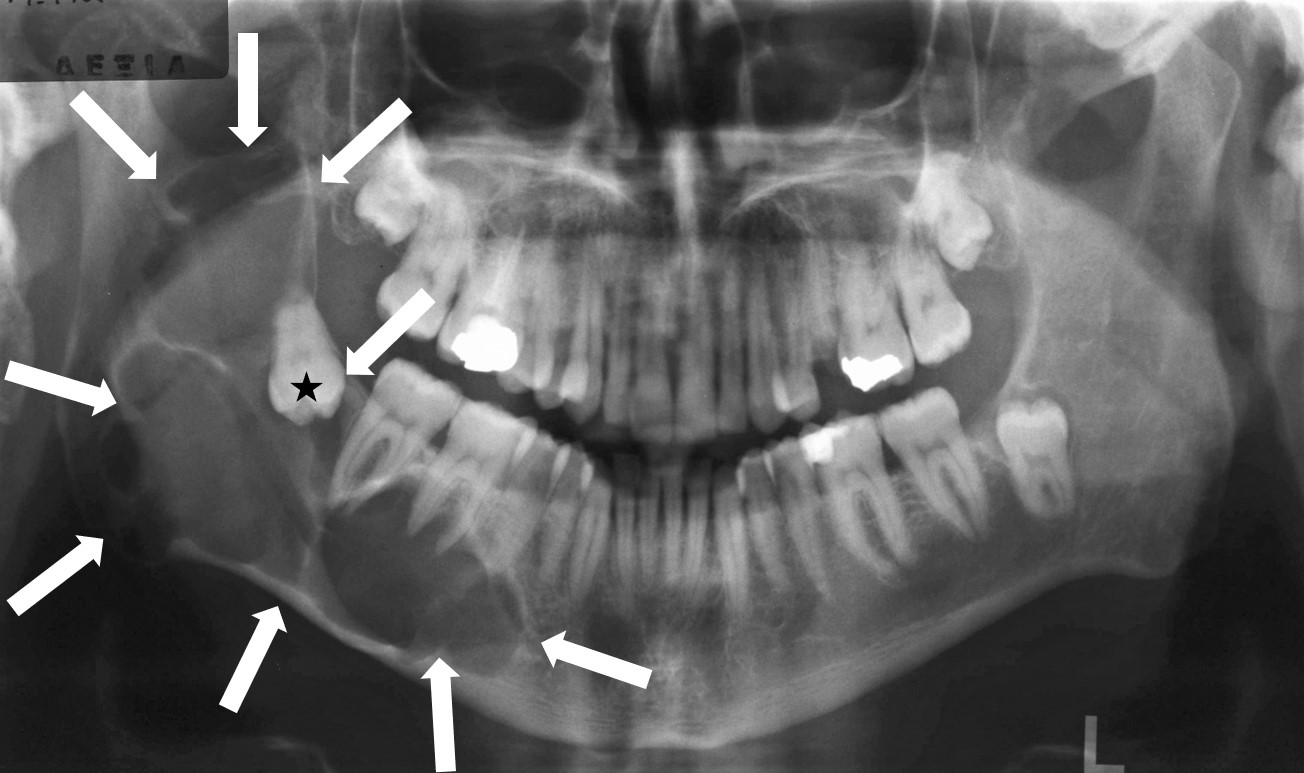

Ένα έγκλειστο δόντι (Εικόνα 1) μπορεί να προκαλέσει οξεία φλεγμονή και οδοντοφατνιακό ή τραχηλοπροσωπικό απόστημα, καθώς και μόνιμη βλάβη σε γειτονικά δόντια, ούλα και οστό. Τα έγκλειστα δόντια σχετίζονται με τη δημιουργία κύστεων και όγκων (Εικόνα 2) που μπορούν να καταστρέψουν μεγάλη ποσότητα του οστού των γνάθων προδιαθέτοντας σε εμφάνιση παθολογικών καταγμάτων της κάτω γνάθου ή σε επιπλοκές από το ιγμόρειο άντρο (Εικόνα 3).

Τα συνήθη συμπτώματα που προκαλούνται από τα έγκλειστα δόντια είναι πόνος και πρήξιμο που οφείλονται σε φλεγμονή των γύρω ιστών. Τις περισσότερες φορές τα έγκλειστα δόντια δεν αντιμετωπίζονται παρά μόνο όταν παρουσιαστούν συμπτώματα. Άλλες φορές και ειδικά σε νεαρές ηλικίες (16 ως 25 ετών) ενδείκνυται η προληπτική αφαίρεσή τους, όταν ακτινογραφικά μπορούν να προβλεφθούν πιθανά μελλοντικά προβλήματα (Εικόνα 4).